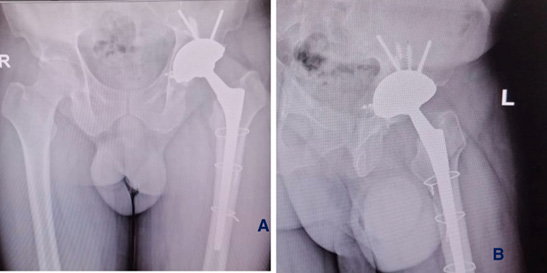

The patient gave written, informed consent to have this case report published. The patient was a 52-year-old male who presented with progressively worsening left hip pain and increasing difficulty in ambulation. He had undergone a Total Hip Arthroplasty (THA) elsewhere for Avascular Necrosis (AVN) secondary to a femoral neck fracture. Within two months of the primary surgery, radiolucent lines began appearing around the acetabular component. By five months, his symptoms had significantly worsened, and repeat radiographs revealed abduction failure and loosening of the acetabular cup across all three DeLee and Charnley zones (Figure 1).

Figure 1: Plain radiograph showing pelvis with both hips (anteroposterior view). (a) 2-month post-operative X-ray showing radiolucent lines, (b) 5-month post-operative X-ray showing failure and loosening, (c) abduction failure of the acetabular component, and preoperative planning.